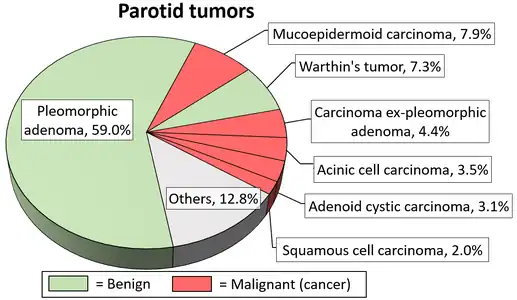

Diagrams by Mikael Häggström - ↑ Ghom AG; Ghom SA (1 July 2014). Textbook of Oral Medicine. JP Medical Ltd. p. 606. ISBN 978-93-5152-303-1.